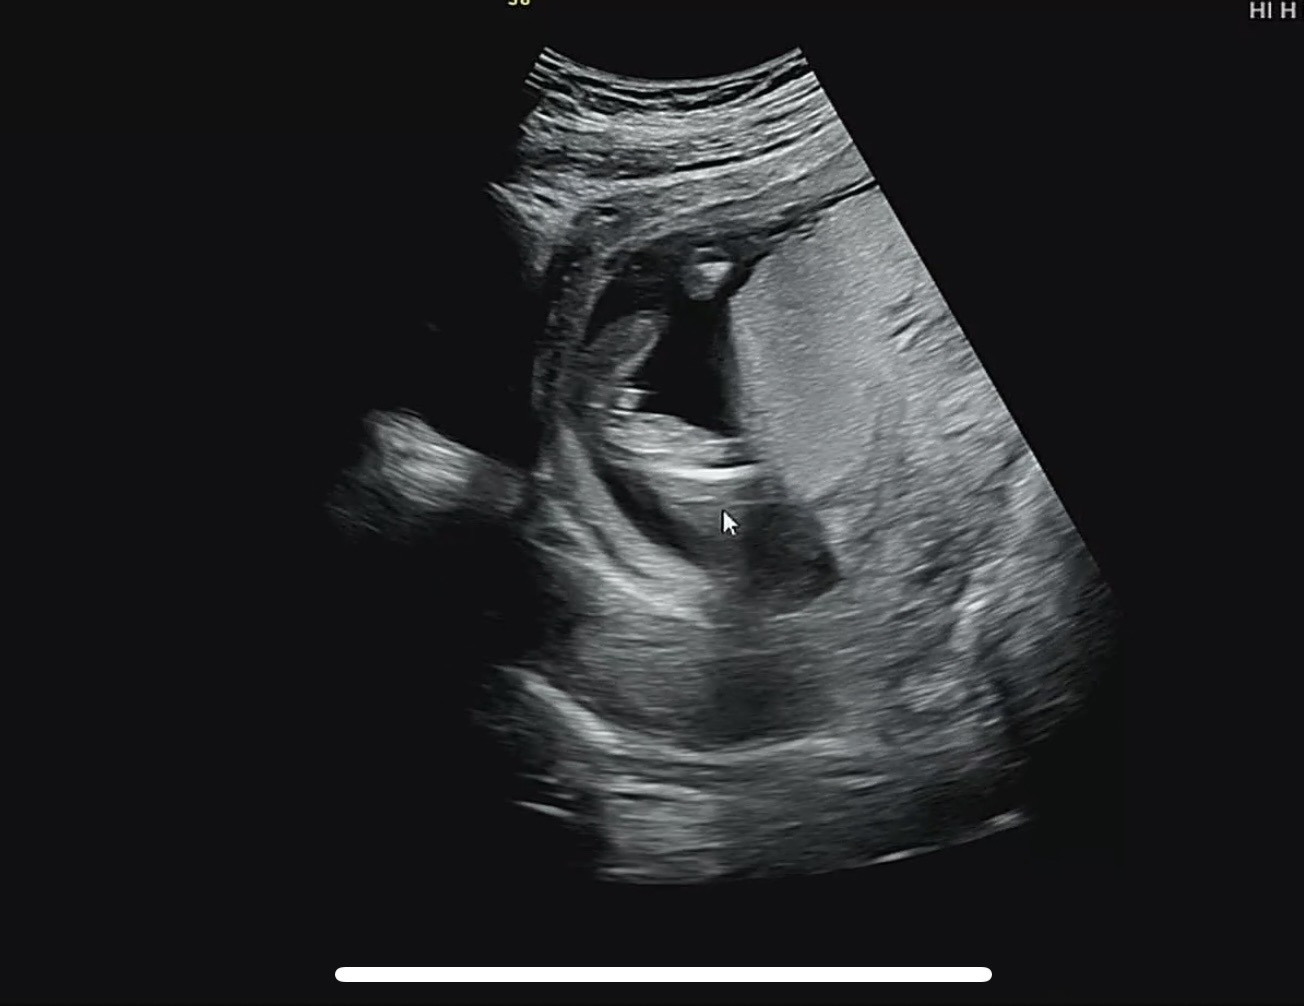

16주1일차 - 의사샘은 딸같다는데…

둘째맘이에요. 의사샘은 딸 같다는데 튀어나온 게 계속 거슬리네요 ㅠㅋㅋ 대음순이 좀 큰 거 같다고는 하시는데 빌리엄마아빠 눈에는 어떻게 보이시나요?